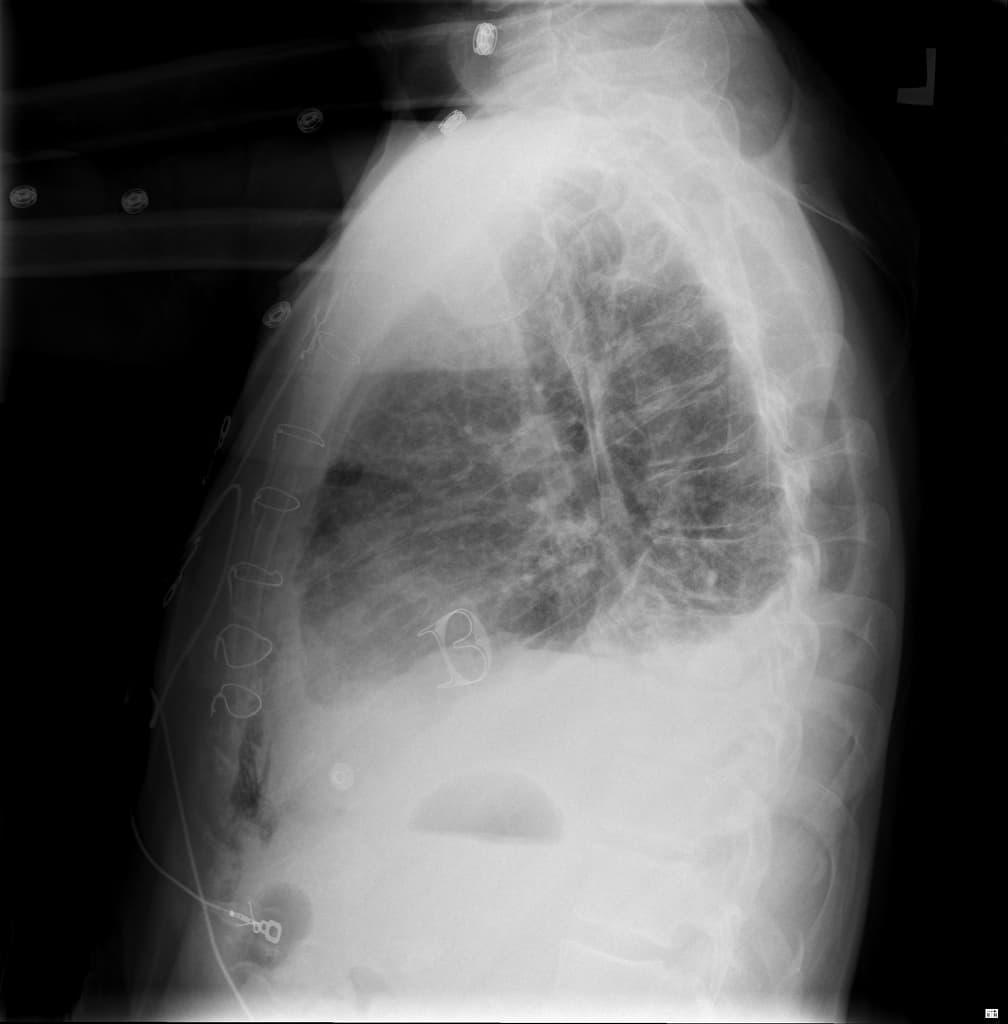

- Tràn khí màng phổi bên phải mức độ nhẹ và dịch màng phổi.

- Gãy xương sườn phải các số 10, 11 và 12, nhưng không có đoạn xương chìm (flail segment).

- Xẹp một phần thùy dưới phổi phải, kèm các khoảng chứa khí dạng nang trong nhu mô phổi, đại diện cho các tổn thương rách phổi (lung lacerations).

- 1.Dập phổi kèm rò khí

- 3.Vỡ cơ hoành kèm thoát vị phổi

Unilateral pulmonary edema from acute mitral regurgitation

Aspiration Pneumonia in a Trauma Patient (Viêm phổi hít do chấn thương)